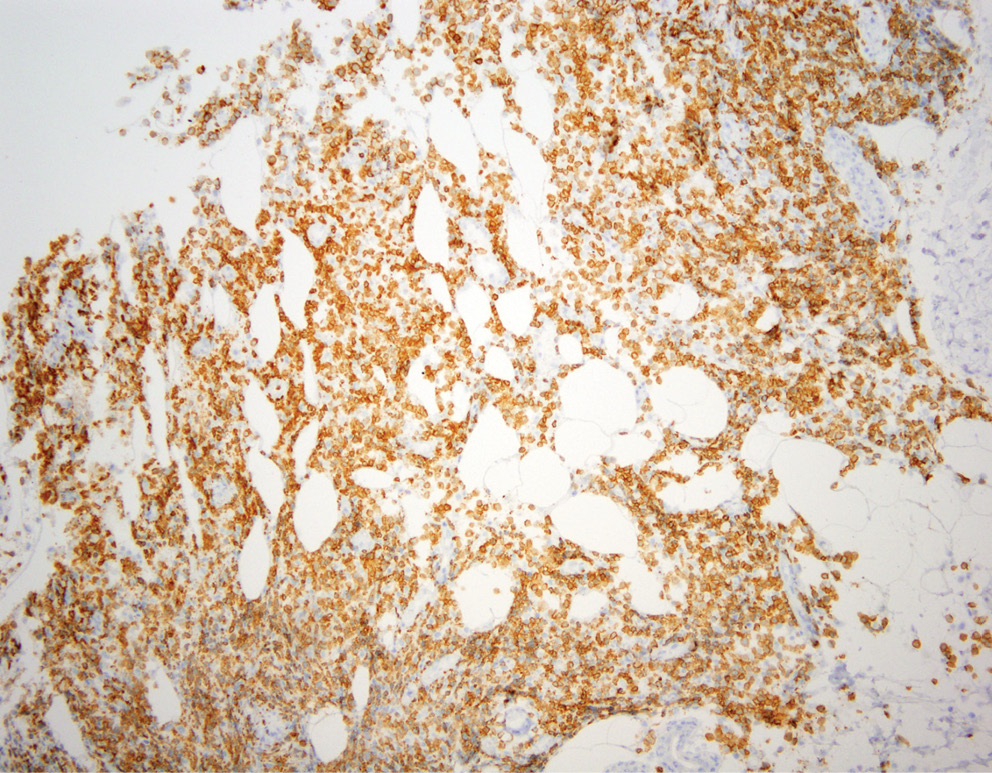

Учитывая отсутствие в биоптате признаков васкулита, гистологический материал пациента был направлен на пересмотр в НИИ онкологии им. Н.Н. Петрова, где было выполнено иммуногистохимическое исследование с антителами ALK, DSF3, CD3, CD4, CD8, CD20, CD30, CD56, Ki-67. По результатам исследования в дерме определялись плотные крупноочаговые инфильтраты, расположенные преимущественно в средних и глубоких отделах дермы и проникающие в дольки подкожной жировой клетчатки (рис. 3). Инфильтраты состояли из крупных лимфоидных клеток с иммунобласто- и центробластоподобной морфологией (рис. 4) и малых лимфоцитов. Крупные лимфоидные клетки экспрессировали CD3+, CD4+ и CD30+, были негативны к ALK (рис. 5–7). Ki-67 (индекс пролиферативной активности) был положителен преимущественно в крупных лимфоидных клетках и составлял примерно 30% всех клеток инфильтрата (рис. 8). Гистологические изменения и иммунофенотип опухолевых клеток соответствовали ЛиП типу С.

Рис. 7. Микрофотография, ×40, иммуногистохимическое исследование с применением анти-CD30 антител. В инфильтрате определяются крупные лимфоидные клетки, экспрессирующие CD30

Fig. 7. Microphotograph, ×40, immunohistochemical assay with anti-CD30 antibodies. In the infiltrate large lymphoid cells with positive CD30 expression